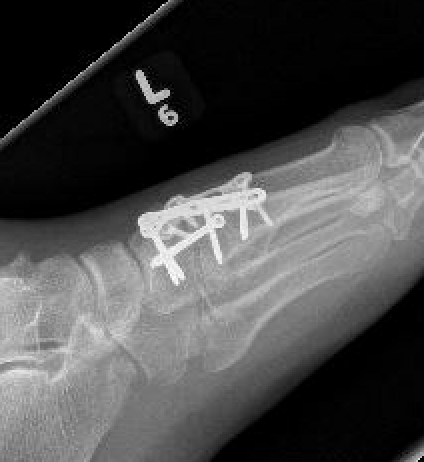

Screw fixation

AP view

- 1st metatarsal to medial cuneiform - screw

- 2nd metatarsal to intermediate cuneiform - screw

- medial cuneiform to base of second metatarsal - screw

+/- medial cuneiform to intermediate cuneiform - screw

Bridge plate to 1st TMT and second TMT with Lisfranc screw